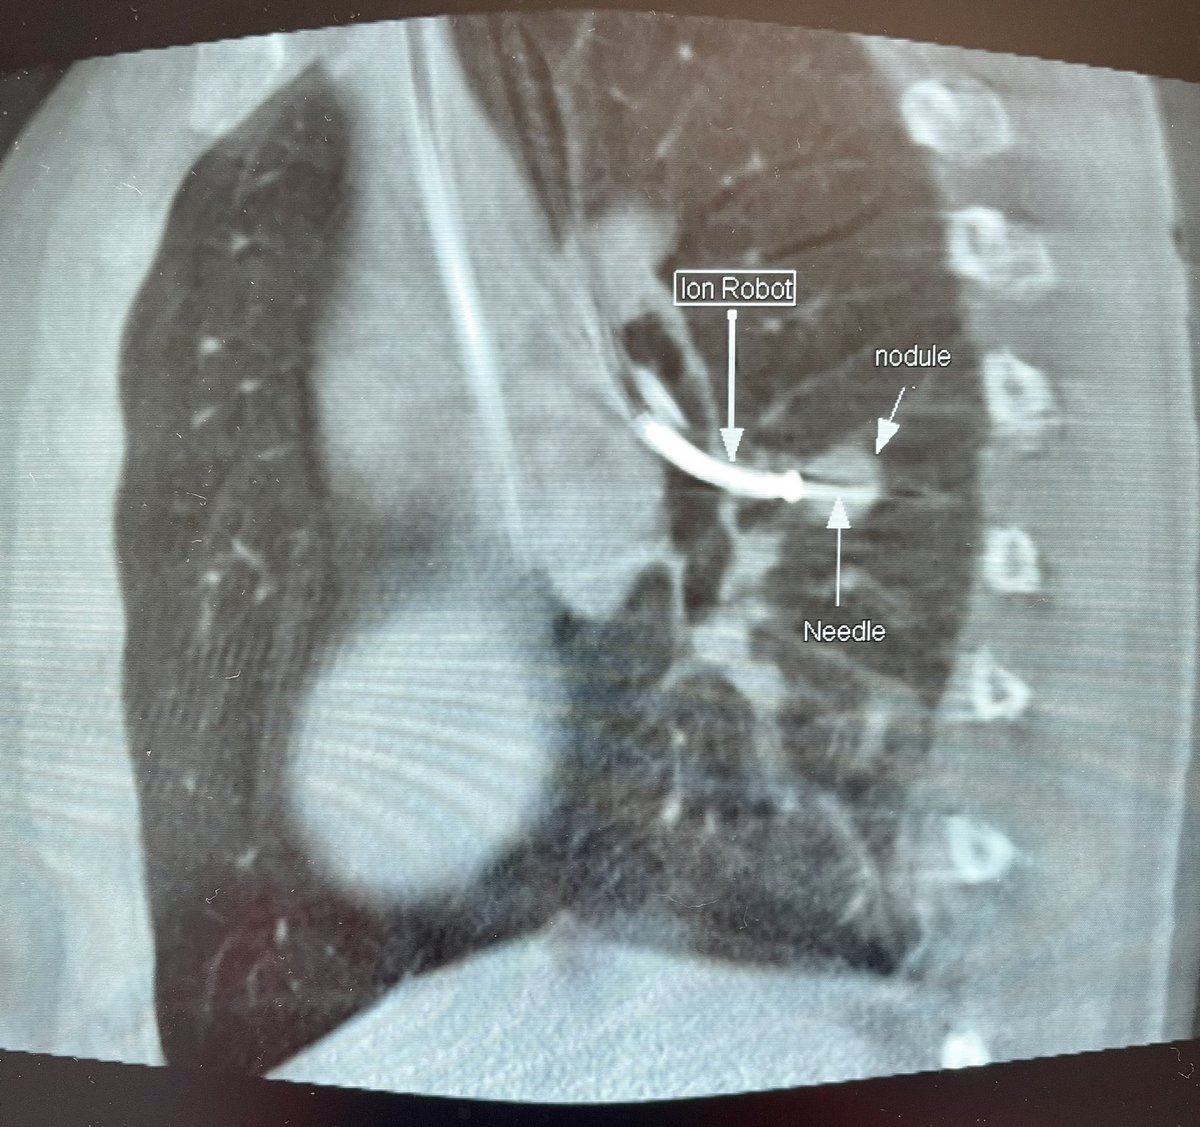

Ramsy Abdelghani, MD@Rabdelgh·

Cool case: 4.5mm partially solid PET-Avid LLL nodule. Used High PEEP/Tidal volume and wedged left side up to decrease dependent atelectasis. Navigated with Ion and adjusted with Philips CBCT. ROSE positive for Adenocarcinoma. Exciting times in lung cancer care! #ION #cbct